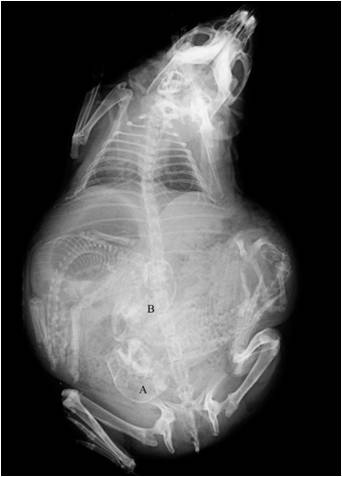

传统数字射线技术为间接探测技术,利用闪烁体进行转换X射线,具有如下问题:较差的分辨率;在高能条件下图像结果不清晰;数据采集速度低;重影问题严重等。目前最先进数字射线成像技术为碲化镉直接将X射线转换为电子信号,优点如下:动态范围大;近乎完美的空间分辨率;快速检测;双能量成像;低剂量有良好的成像效果.

03.png

Cd(Zn)Te-CMOS

300 kVp

100 um

300fps,检测焊缝速度高达1.8米/分钟

支持编程和开发,Labview等